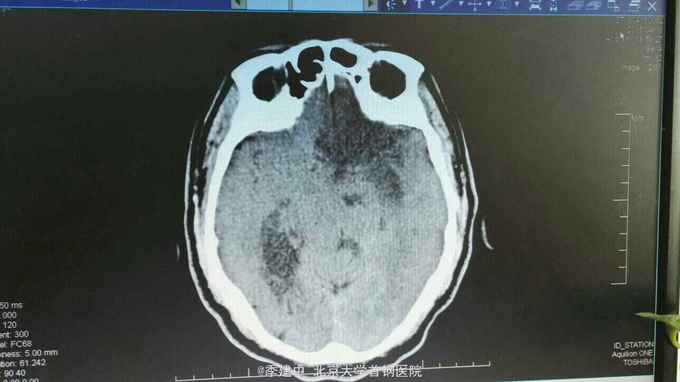

诊断:脑梗死 高血压3级 极高危 2型糖尿病 高脂血症 治疗:入院后给予抗血小板聚集、改善脑供血、清除自由基、扩容,脱水及对症支持治疗。2016.4.16接班后查房发现患者呼之无应答。查体:T:37.7℃;P:95次/分;R:20次/分;BP:202/90mmHg。 深度嗜睡至浅昏迷,呼吸节律尚规整,查体不合作。双侧眼球居中,双侧瞳孔不等大,左侧直径3.0mm,右侧直径约1mm。右侧鼻唇沟浅。双侧Babinski'sign、双侧Chaddock'sign(+)。右侧肢体无自主活动。双肺未闻及干湿啰音,心率95次/分,律齐,双下肢无浮肿。急诊复查头CT示:多发脑梗死,左侧额颞顶叶大面积梗死,建议MRI检查进一步明确。阅片可见侧脑室受压明显,中线移位,有脑疝形成。请神经外科急会诊,建议行去骨瓣减压术。告知患者家属上述情况,家属同意转神经外科行急诊去骨瓣减压术。